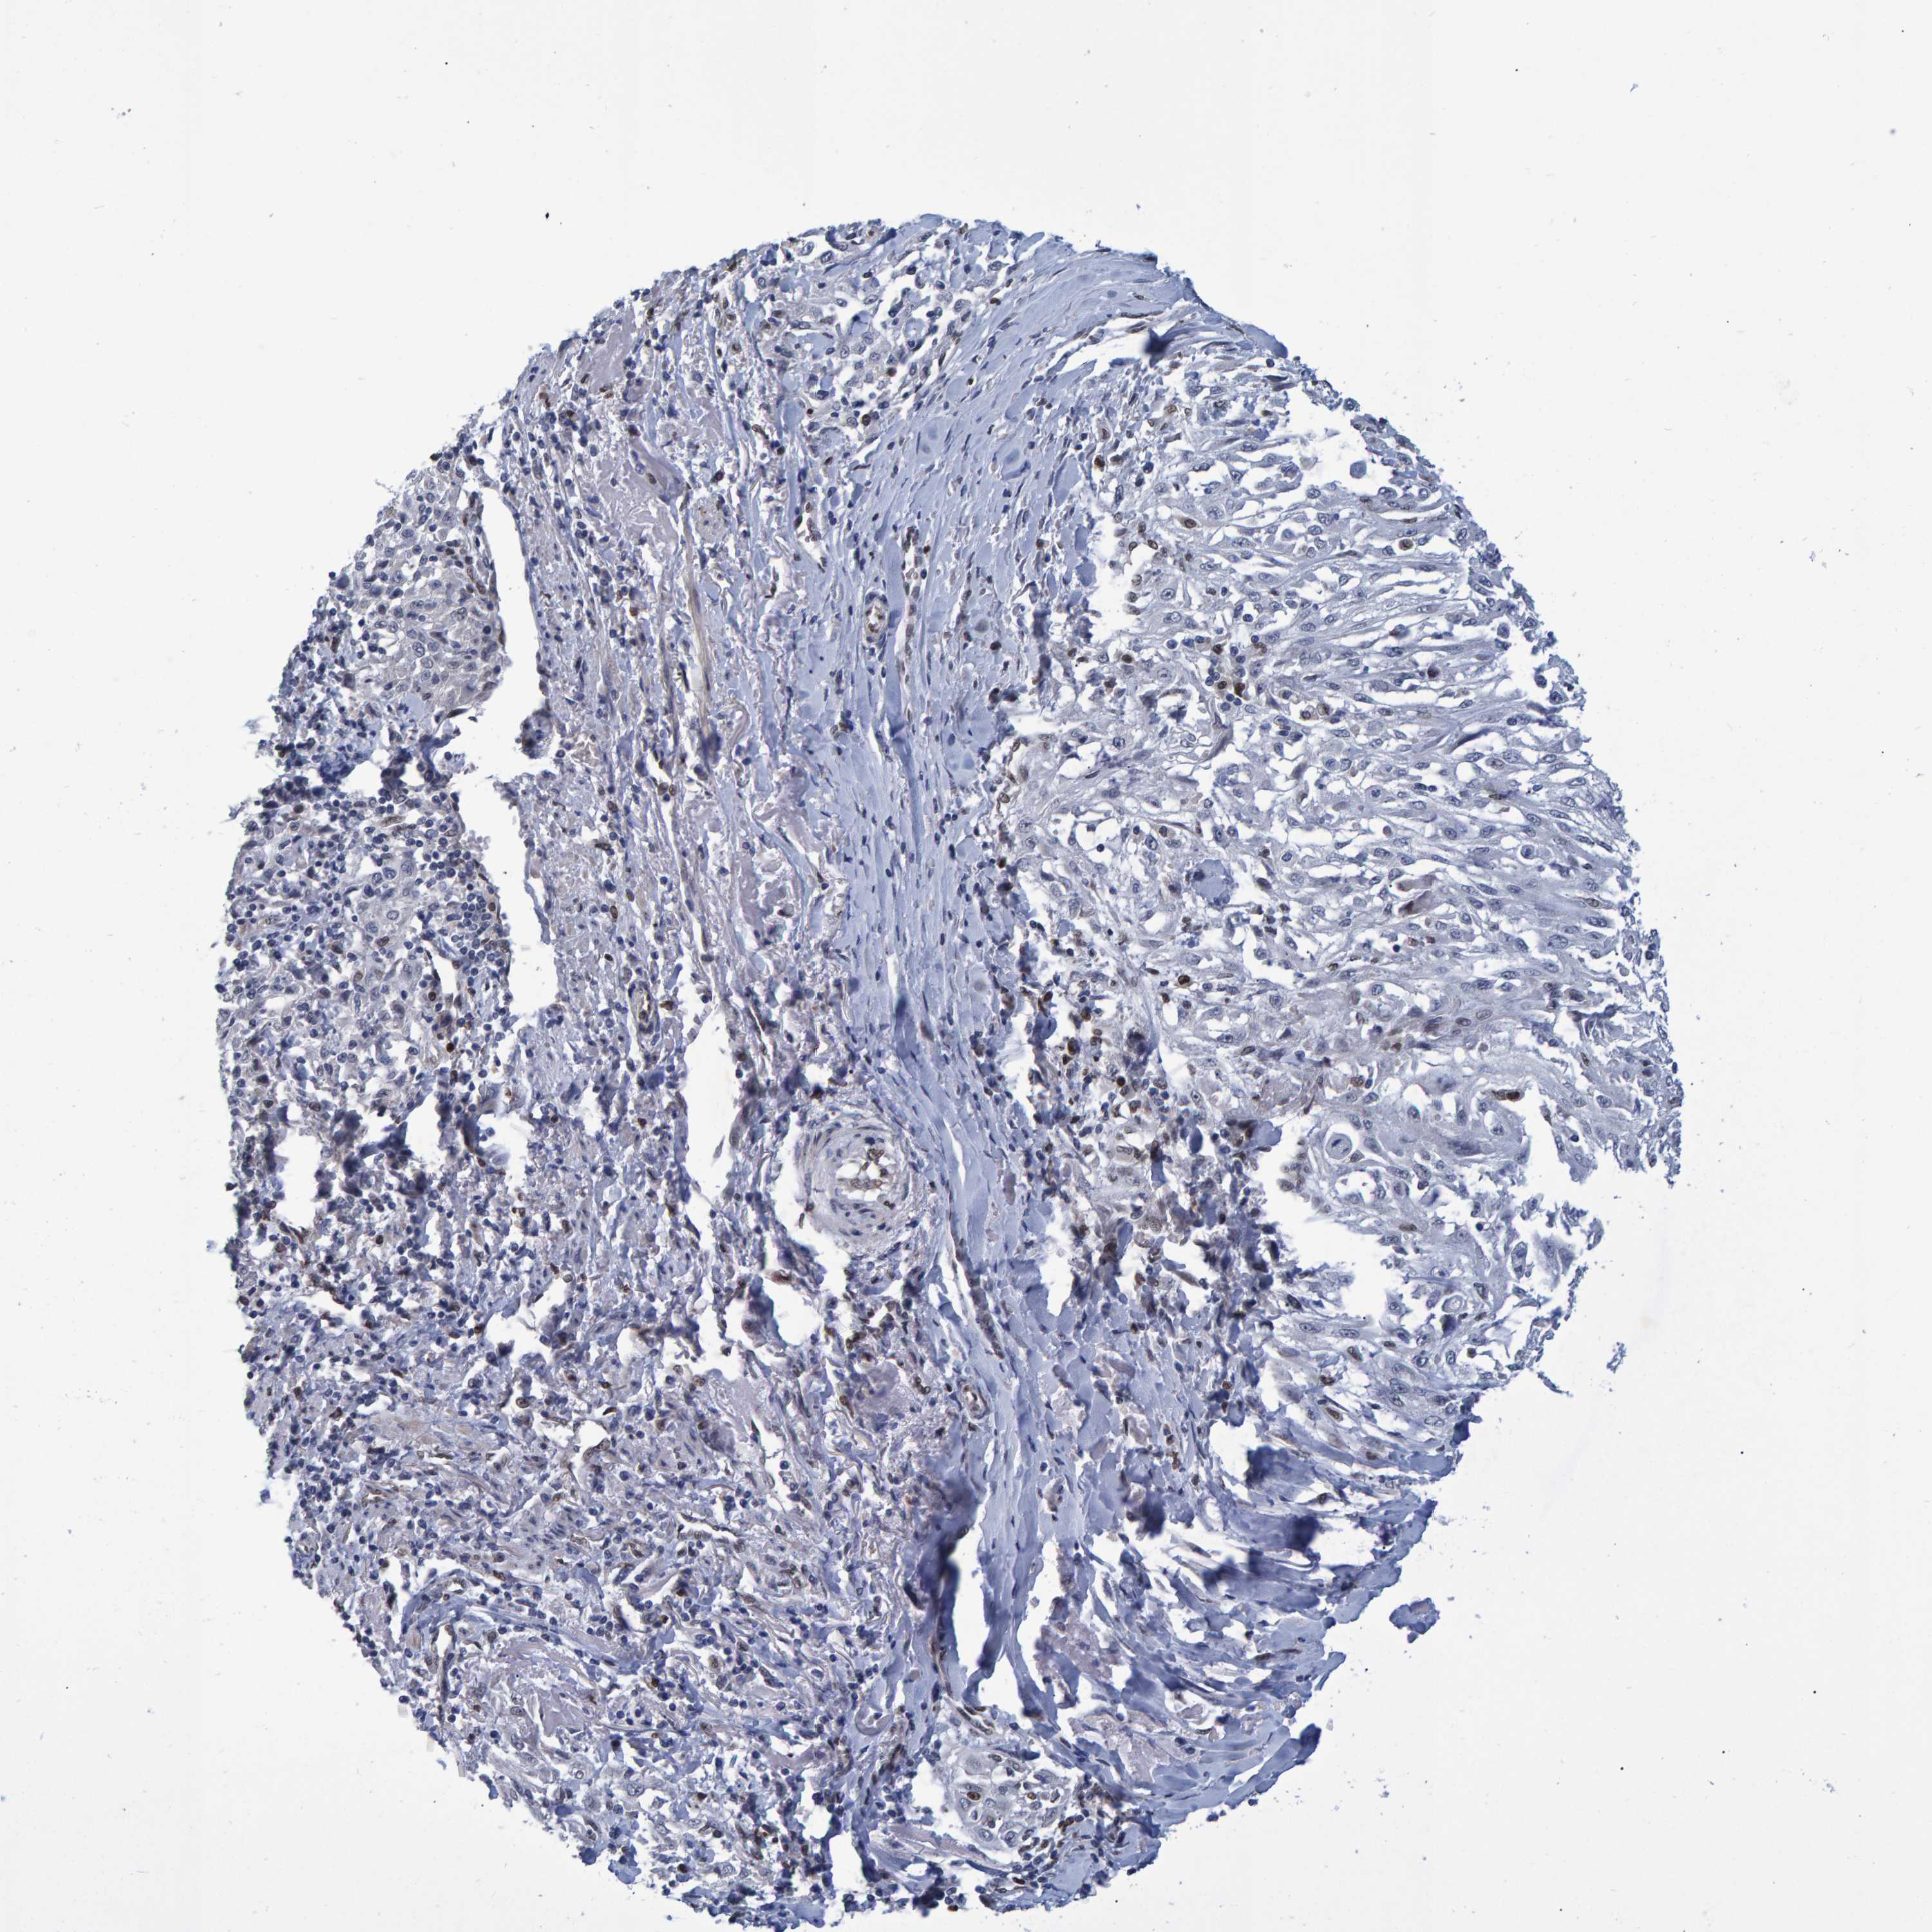

SKIN CANCER - Protein expressioni

A mouse-over function shows sample information and annotation data. Click on an image to view it in a full screen mode. Samples can be filtered based on level of antibody staining by selecting one or several of the following categories: high, medium, low and not detected. The assay and annotation is described here.

Each image is clickable and will lead to virtual microscopy that enables deeper exploration of all samples and also displays staining intensity scores, fraction scores and subcellular localization as well as patient and tissue information for each sample.

Antibody CAB022602

Staining

High

Medium

Low

Not detected

Intensity

Strong

Moderate

Weak

Negative

Quantity

>75%

75%-25%

<25%

None

Location

Nuclear

Cytoplasmic/membranous

Cytoplasmic/membranous,nuclear

Squamous cell carcinoma, NOS

Squamous cell carcinoma, metastatic, NOS

Basal cell carcinoma